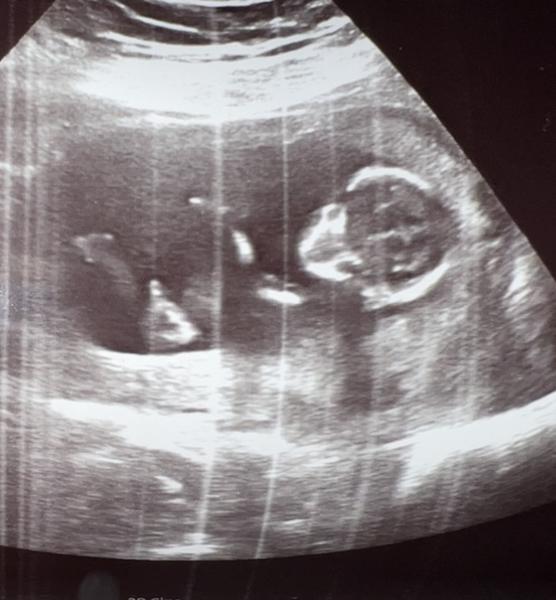

jedna fotka z prvního screeningu ve 13. tt a druhá při kontrole v 17. tt.